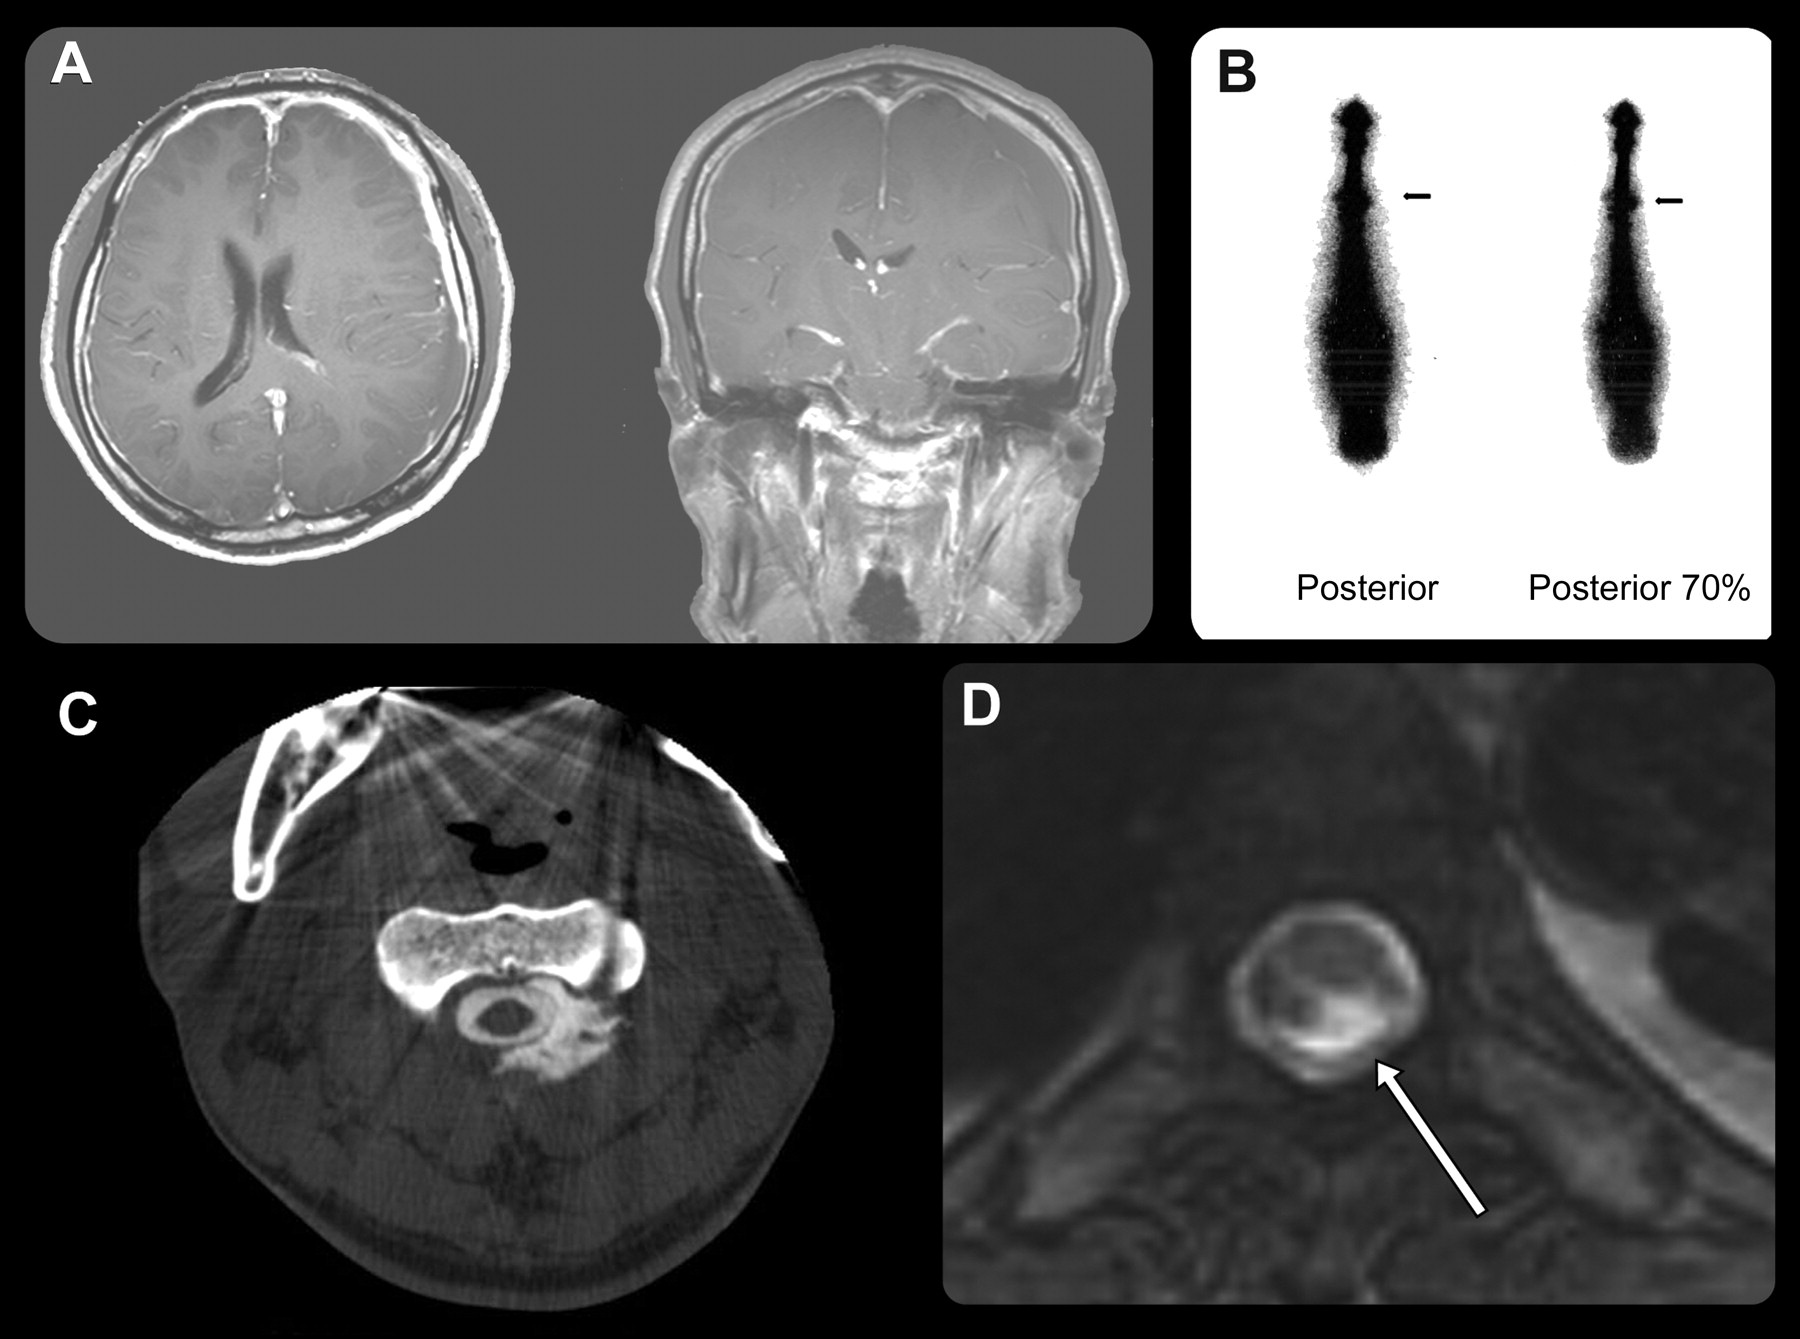

1999年1月至2009年12月,我们61个连续的患者治疗诊断为硅根据国际头痛头痛疾病分类标准归因于自发性脑脊液压力(或特发性)低。15在大多数患者中,脑MRI显示强烈的对比度增强和增厚pachymeninges,兼容的典型影像学检查硅(图1)。其他先生发现包括下行扁桃体的下垂,海绵窦充血,和垂体腺肿大。更准确的诊断,增加腰椎脑脊液51的61名病人进行了研究。CSF漏准确的定位网站,我们评估脊柱MRI,包括fat-suppression t2加权图像CT myelographic或放射性核素cisternographic图像(图1)。硅氮诊断后,病人被建议卧床休息至少两周。

56例(23男人和33个女人;平均年龄39.6岁;范围22 - 69年)被纳入本研究。临床上,55例(98.2%)显示直立性头痛发作的症状。其他硅的表现包括恶心,呕吐,颈部僵硬、耳鸣、视力模糊、复视、精神状态改变。在所有患者脑部MRI进行早期诊断。扩散pachymeningeal增强脑部MRI是最常见的发现,并在48例。然而,8例没有pachymeningeal增强明显。硬脑膜下血肿被发现在13个患者和18例观察扁桃体的向下位移。12例MRI显示一个删除prepontine水箱。 Spinal MRI was performed in 27 patients, CT myelography in 19, and radioisotope cisternography in 33. Spinal neuroimaging such as whole spine MRI including fat-suppression images or CT myelography and radioisotope cisternography revealed a spinal CSF leak site in 37 of 56 patients (图1)。脑脊液漏的位置如下:颈,6例;cervico-thoracic, 15;midlower胸,8;腰,10;和未知,17 (表1)。由于质量效应,8慢性硬膜下血肿患者接受了毛刺和排水洞环钻术。